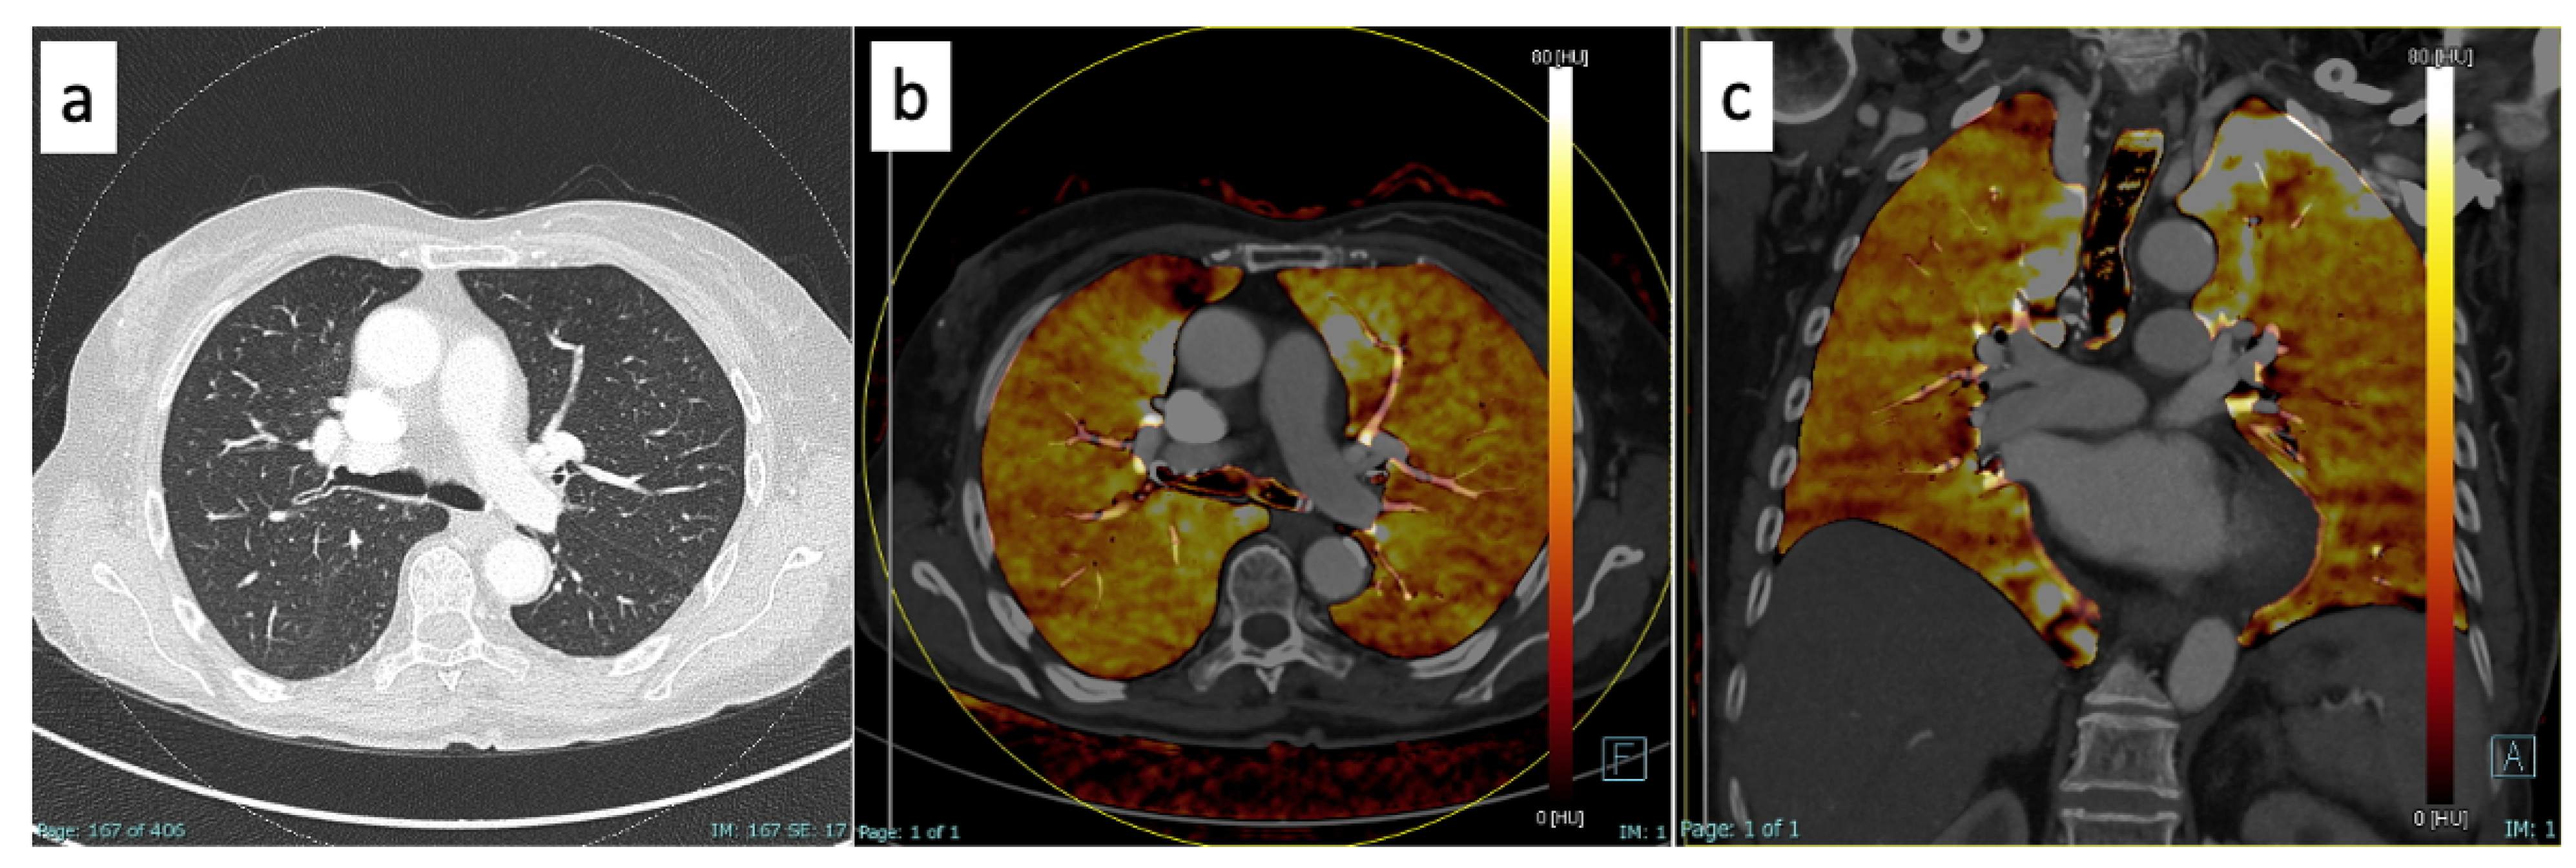

2.2. Imaging Acquisition

2.3. Imaging Post-Processing